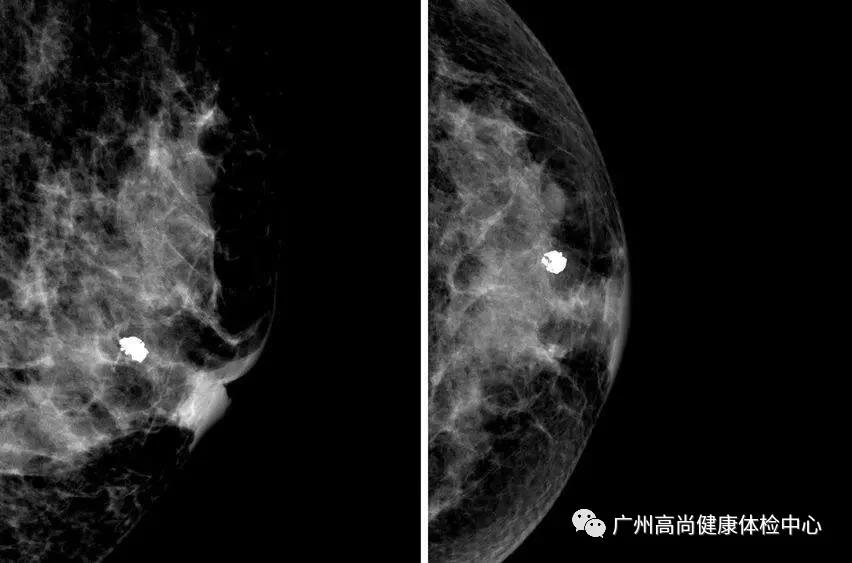

乳房的鈣化點(diǎn)大部分都是良性的,或伴有其他良性病變,如乳腺增生。所以,乳房鉬靶上如果看到大大的白點(diǎn),通常就是良性鈣化點(diǎn),如纖維腺瘤就常常會(huì)在鉬靶的影像上出現(xiàn)爆米花狀的粗糙大白點(diǎn)。

2、惡性鈣化

當(dāng)癌細(xì)胞不受控制地生長(zhǎng),這一群癌組織會(huì)變得很擁擠,導(dǎo)致里面小部分的細(xì)胞會(huì)因組織缺氧而壞死。這時(shí),我們身體無(wú)法清除壞死的組織,這些細(xì)胞就變硬而形成鈣化點(diǎn)。

因此,惡性鈣化點(diǎn)的特點(diǎn)是:聚集很緊密,簇聚于局部區(qū)塊,且鈣化點(diǎn)很小,形狀不規(guī)則,每個(gè)點(diǎn)都不太一樣,或有針尖狀、小桿狀、分叉狀、簇狀及泥沙樣多屬于惡性病變。

每一個(gè)檢查設(shè)備都有各自擅長(zhǎng)的地方,由于乳腺鉬靶是把乳房夾起來(lái)照X線,鈣質(zhì)可以吸收較多的X線,因此其主要優(yōu)勢(shì)在于對(duì)微小鈣化檢出敏感,可以降低乳腺癌患者的死亡率,是歐美國(guó)家乳腺癌篩查優(yōu)選的影像檢查。但相對(duì)比超聲檢查,局限性在于對(duì)致密型乳腺敏感度低。